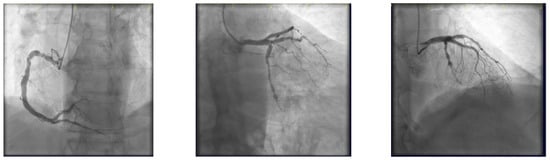

- Engage the left coronary artery with an EBU 4.0/8F guiding catheter. Wiring the three branches of the trifurcation (Floppy guide wires in LAD and RI, Hydrophilic guide wire in LCX) (Figure 14).